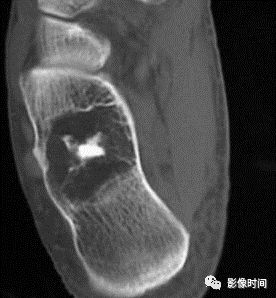

五、骨和软组织钙化

(一)瘤软骨钙化:瘤软骨常表现为环状钙化, 是诊断软骨类肿瘤较为可靠的影像学征象。环状钙化形成于环状软骨、以及软骨小叶边缘的软骨基质。钙质沉着可呈小点状、小条状、半环状或弧形;亦可浓密相连、重叠呈菜花状。钙化环的形态和密度可反映瘤组织分化程度, 通过观察钙化环的形态和密度,有助于良恶肿瘤的鉴别。

良性瘤软骨之瘤细胞分化好、生长缓慢、血供充分, 钙化环完整,密度高, 边缘清楚。良性软骨类肿瘤如骨软骨瘤(图 35)、软骨母细胞瘤(图 36)、内生软骨瘤(图 37)等均可于瘤组织内发生环形钙化。

恶性瘤软骨则呈密度淡薄, 边缘模糊的不规则钙化,恶性骨肿瘤的环形钙化,最多见于软骨肉瘤(图 38),其次是骨肉瘤。CT 是发现肿瘤内软骨钙化最为敏感的检查方法。

图 37  瘤软骨钙化:内生软骨瘤